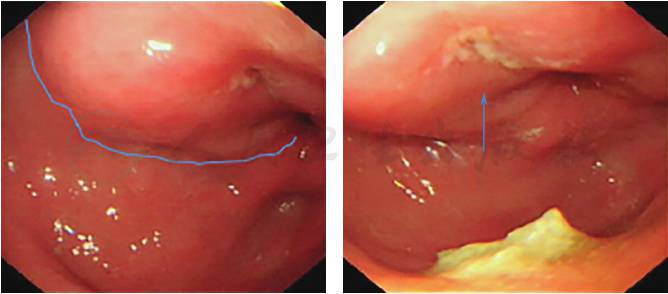

超声胃镜:①胃窦前三层增厚伴壁外淋巴结肿大;②胃潴留(图2)。再次病理检查提示胃(窦)黏膜组织呈慢性炎症改变伴急性活动,少数腺体肠上皮化生并呈轻度不典型增生,另见较多纤维肉芽组织及炎性坏死物。

图2 超声胃镜检查